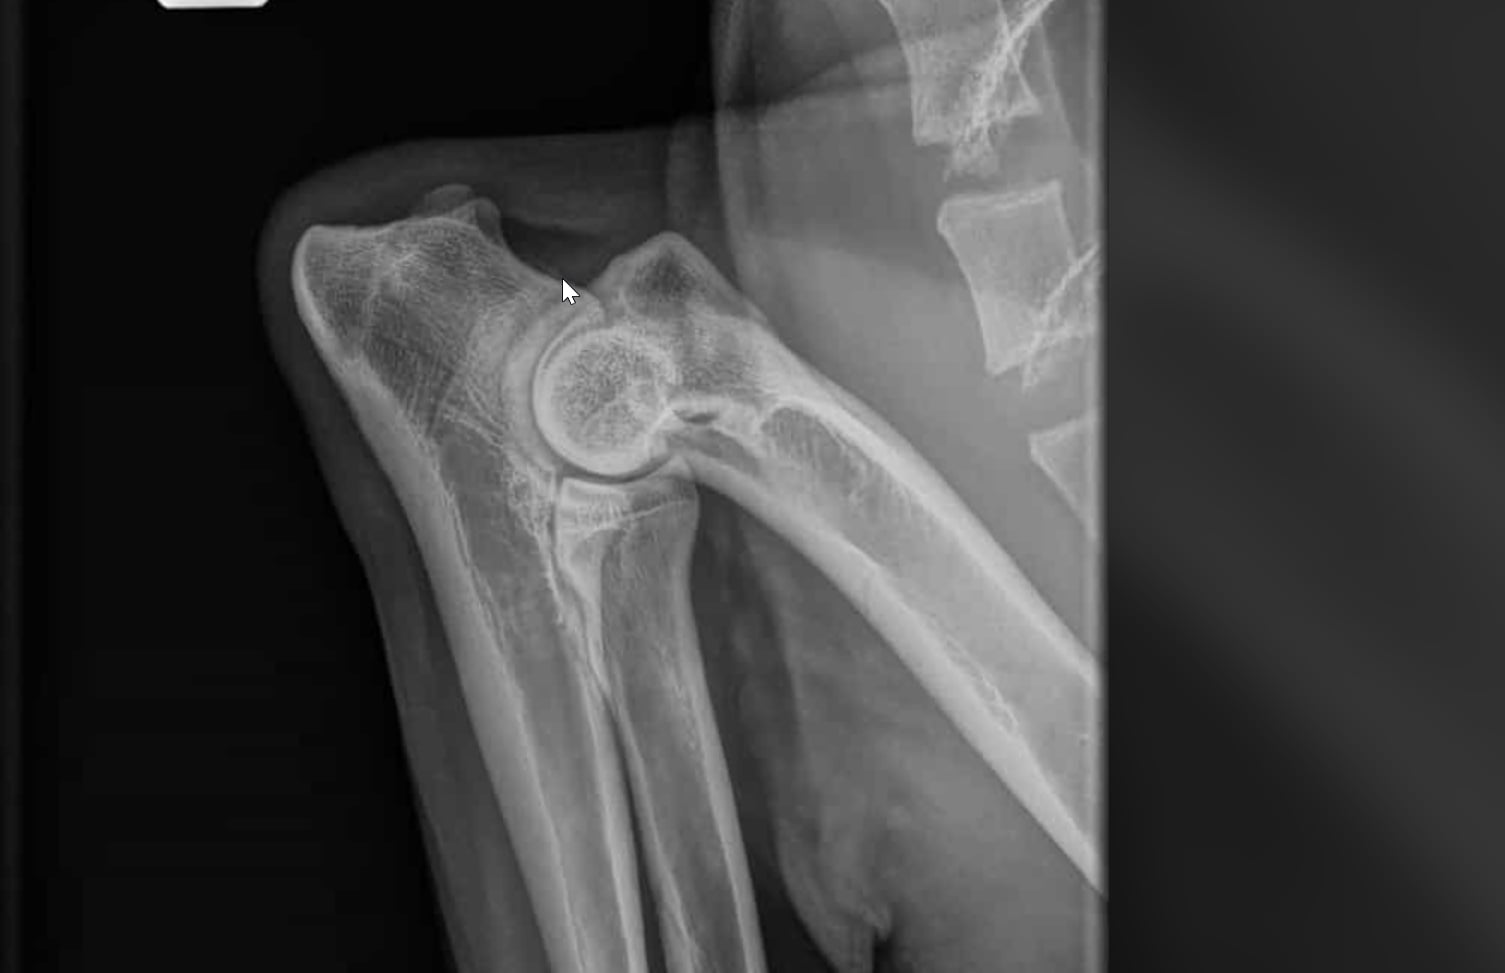

hiiren osoittimesta vasemmalle/ylös lähtee osteofyytti luun pinnassa, joka ei mikään koiran kannalta iso. Todennäköisesti seurausta kasvuaikana olleesta pienestä inkongroensista ja nivel päässyt liikkumaan liikaa.